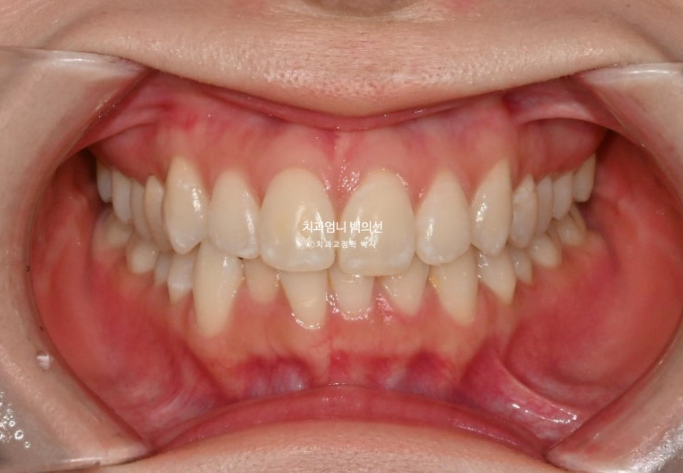

25.01

위 아래 치아중심선이 어긋나 있고 아래 앞니 하나가 솟으면서 뒤로 들어가 있습니다.

어금니 교합은 좋죠.